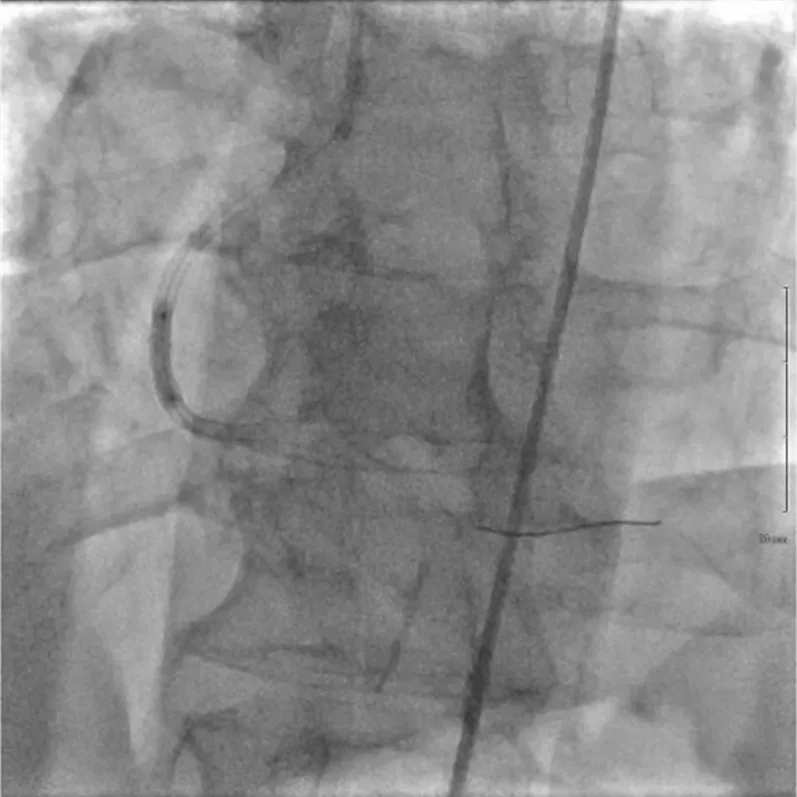

➤ 使用OPN球囊(3.0 mm,40 atm)进行积极预扩张(图3)。

图3